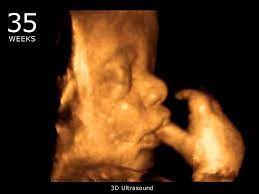

/ 4D Ultrasound Pictures 35 Weeks - Got My 3d 4d Ultrasound At 35 Weeks Too Cute Not To Share January 2020 Babies Forums What To Expect - You'll notice that what you see varies a lot by the number of weeks of gestation.

4D Ultrasound Pictures 35 Weeks - Got My 3d 4d Ultrasound At 35 Weeks Too Cute Not To Share January 2020 Babies Forums What To Expect - You'll notice that what you see varies a lot by the number of weeks of gestation.

Baby impressions is an elective 3d 4d ultrasound imaging facility. Fetal measurements (by request) hear & see baby's heartbeat. 3d & 5d ultrasound images and 4d ultrasound video can be obtained at any stage. Baby's estimated weight and position. 30 weeks is best for 3d/4d images of what your baby will look like after it is born. Water can improve the quality of an ultrasound. At this stage, the baby has put on some weight and filled out to make features more visible, yet still enough fluid in front of baby's face to obtain great images. You'll notice that what you see varies a lot by the number of weeks of gestation. It was a very special day for my husband and i. In addition to 3d 4d ultrasound, baby bloom is known for our spectacular hd live ultrasound imaging. We do not perform medical ultrasounds. When i was 31 weeks i went back for our first 3d/4d ultrasound and it was even more special being able to see my son's face for the very first time. Book now *free rescan if face can't be seen at all.

Ultrasound Sessions Baby To Be 3d from images.squarespace-cdn.com The best proof is our gallery of weekly 3d ultrasound images taken from 13 weeks and until up to 39 weeks. Even if they're squished and you don't get the best pictures. Baby impressions is an elective 3d 4d ultrasound imaging facility. At this stage, the baby has put on some weight and filled out to make features more visible, yet still enough fluid in front of baby's face to obtain great images. Baby's first photos 112 e. In these final weeks before your baby's birth, several subtle changes are taking place that will prepare. 4d or 4 dimensional scans build on the technology of 3d scans. They were the first to tell me that i was having a baby boy at 16 weeks.